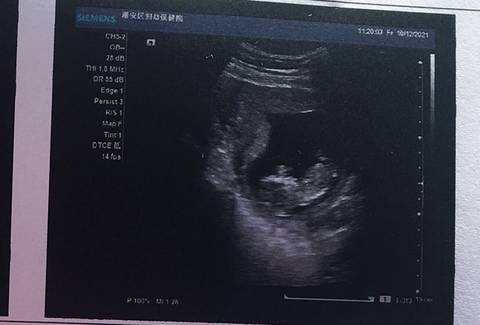

12周nt,好奇是男孩还是女孩,有经验的姐姐们帮忙看下

嗨到停不下 2021-12-11 10:00